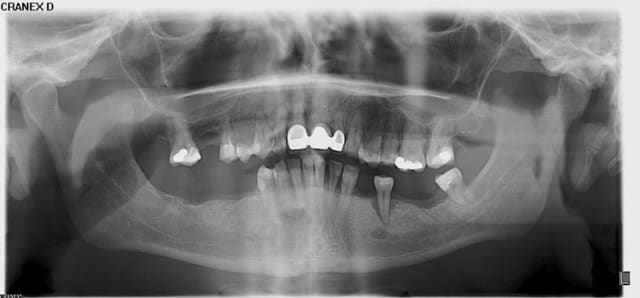

Voici

A toi de juger si la paro peut encore qqch pour cette patiente

A titre purement informatif : mobilité de type II et III de partout ;-)

c est vrai que pour ta patiente cest cuit . Mais n oublie pas que la raison qui lui a fait perdre ces dents en 10 ans lui fera perdre tes implants en 10 ans . La parodontite est une question de bacteries/predispositions/facteurs de risques ! Si tu nechanges pas ca tu perdras tes implants

Il et clair Pp que le cas que tu nous montres est dramatique. D'autant plus dramatique que la solution implantaire ne sera malheureusement pas une solution de long terme.

D'un autre côté, les photos cliniques que tu nous joins montrent clairement que même si la patiente a subi un ttt paro il y a 10 ans, elle n'a en toute certitude pas continuer son traitement de maintenance !

Le traitement des parodontites et d'autant plus quand elles ont un caractère aussi aggressif implique un suivi et traitement régulier du patient. Sans cela, c'est l'échec assuré.

Amicalement

Olivier